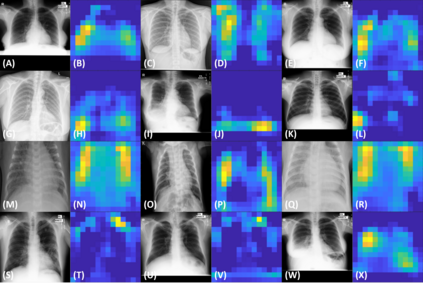

Pulmonary diseases can cause severe respiratory problems, leading to sudden death if not treated timely. Many researchers have utilized deep learning systems to diagnose pulmonary disorders using chest X-rays (CXRs). However, such systems require exhaustive training efforts on large-scale data to effectively diagnose chest abnormalities. Furthermore, procuring such large-scale data is often infeasible and impractical, especially for rare diseases. With the recent advances in incremental learning, researchers have periodically tuned deep neural networks to learn different classification tasks with few training examples. Although, such systems can resist catastrophic forgetting, they treat the knowledge representations independently of each other, and this limits their classification performance. Also, to the best of our knowledge, there is no incremental learning-driven image diagnostic framework that is specifically designed to screen pulmonary disorders from the CXRs. To address this, we present a novel framework that can learn to screen different chest abnormalities incrementally. In addition to this, the proposed framework is penalized through an incremental learning loss function that infers Bayesian theory to recognize structural and semantic inter-dependencies between incrementally learned knowledge representations to diagnose the pulmonary diseases effectively, regardless of the scanner specifications. We tested the proposed framework on five public CXR datasets containing different chest abnormalities, where it outperformed various state-of-the-art system through various metrics.